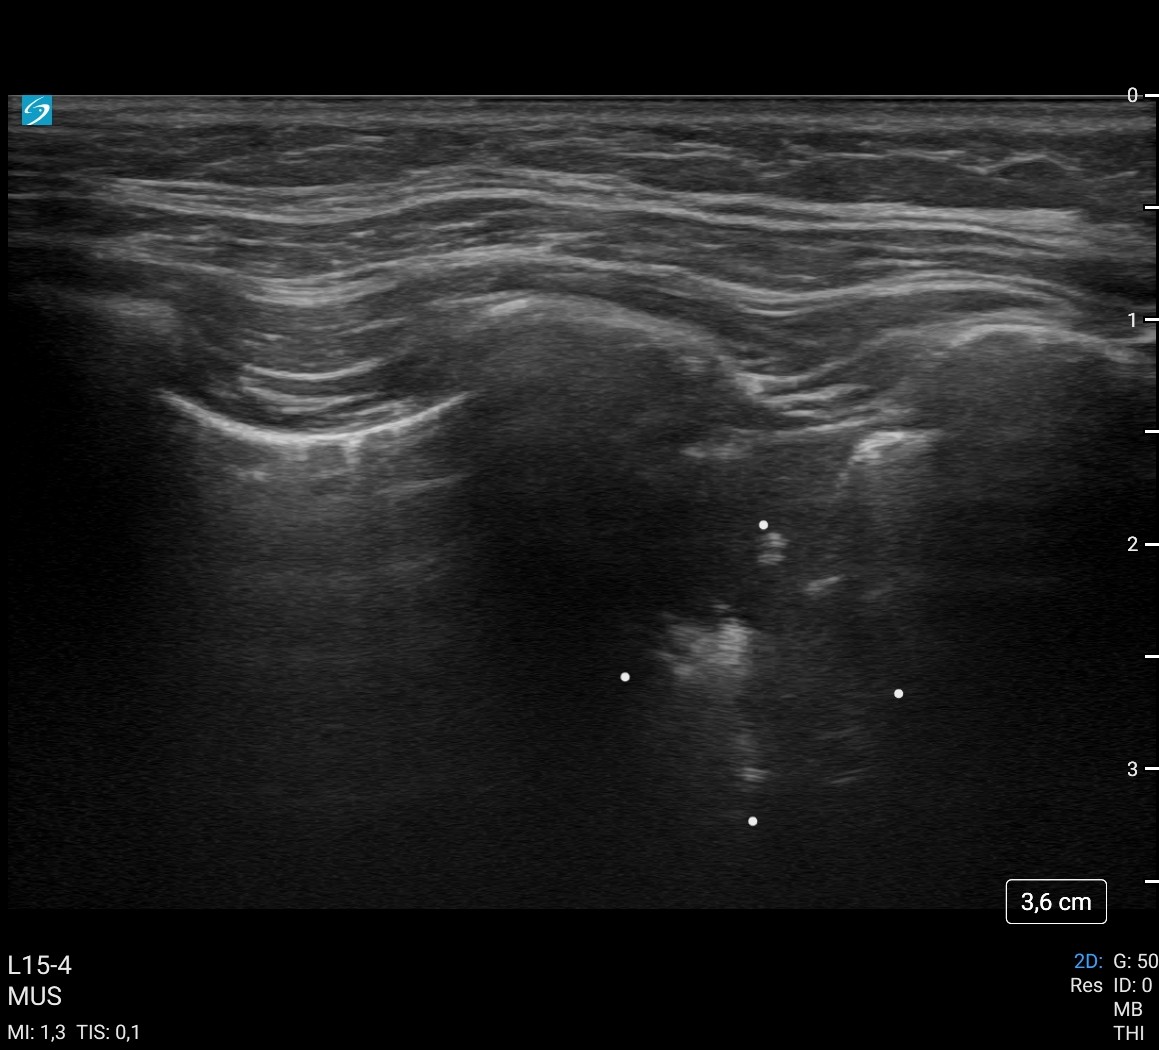

A la exploración física temperatura de 38 ºC, resto de constantes en rango. ORL sin alteraciones. A la auscultación pulmonar, presenta crepitantes en base derecha, por lo que realizamos ecografía pulmonar a pie de cama evitando así radiar a la paciente en una segunda ocasión.

Hallazgos ecográficos

Se objetiva consolidación pulmonar en lóbulo inferior derecho sin derrame asociado.